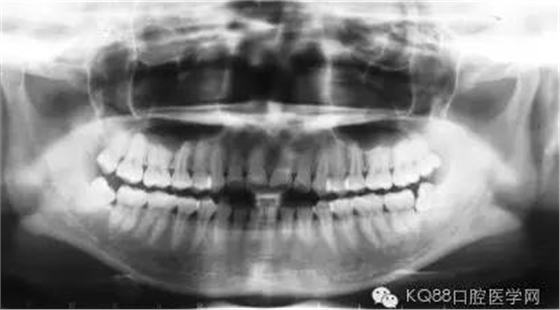

長時間的牙結石堆積最后會造成牙槽骨吸收和牙周袋形成,牙周袋內很容易聚集食物殘渣和細菌。這樣惡化循環(huán),最后的結果是牙齒松動、脫落。

由于不使用牙線、刷牙方式的不正確,或者其他因素(如牙列不齊、口腔內有不良修復體、藥物作用、激素水平的變化)的影響,也許一個人只有牙齦上的結石,沒有牙槽骨吸收的現象,此時只需常規(guī)的潔牙。

當牙齦下存在的牙結石,或有牙槽骨吸收跡象時,常規(guī)潔牙往往無法清除牙齦下的結石,此時需要進行牙周刮治了。

牙槽骨一旦吸收很難再生,所以,牙周刮治的目的是為了防止進一步的牙槽骨吸收,牙周袋形成以及牙齦出血。更有利于牙齒的穩(wěn)固和健康。

經過牙周刮治(包括齦下刮治和跟面平整術)的患者,每3到4個月需要進行一次牙周維護,因為他們牙齦下的堆積結石的幾率比一般人的要高。同時,掌握正確的刷牙方式(每天至少刷兩次),堅持使用牙線,對維護牙周健康也能起到一定的作用。